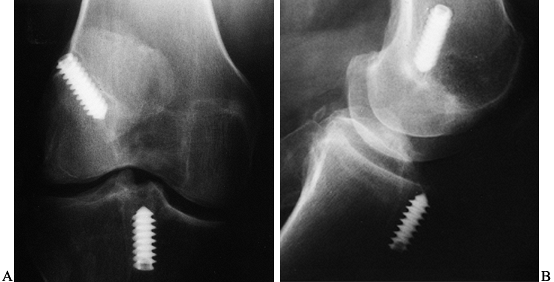

tunnel that originates at the 1 o’clock position in the left knee and

11 o’clock position in the right knee and has a 1- to 2-mm posterior

cortical shell (Fig. 89.15). This provides for

an anatomic and near-isometric position of the graft. Avoidance of

posterior cortical “blow out” is minimized by meticulously clearing the

soft tissue surrounding the “over-the-top” position and confirming the

position with a probe. Use a retrograde femoral offset guide placed

through the tibial tunnel that positions the guide pin 7 mm anterior to

the posterior cortex. This leaves a 2-mm bone shell when a 10-mm reamer

is used to make the tunnel (Fig. 89.16A). Alternatively, one could create an accessory inferomedial portal, place the femoral aimer

through the portal, hyperflex the knee, and drill the femoral socket (Fig. 89.16B).

Figure 89.15.

Sagittal cross section of a femur showing a 7-mm “over-the-top” guide placed over the posterior edge of the notch and a guide pin placed through the guide and into the femur. Overreaming with a 10-mm reamer will leave a 2-mm posterior wall in the femoral socket. (From Hardin GT, Bach BR Jr, Bush-Joseph CA, Farr J. Endoscopic Single-Incision Anterior Cruciate Ligament Reconstruction Using Patellar Tendon Autograft. Surgical Technique. Am J Knee Surg 1992;5:144.) |

Figure 89.16. A: Illustration of a right knee with the “over-the-top” guide placed through the tibial tunnel. B:

Alternatively, place the guide through a low inferomedial portal and, with hyperflexion of the knee, position the guide and drill the pin. This method creates a femoral socket that is not dependent on the position of the tibial tunnel. |